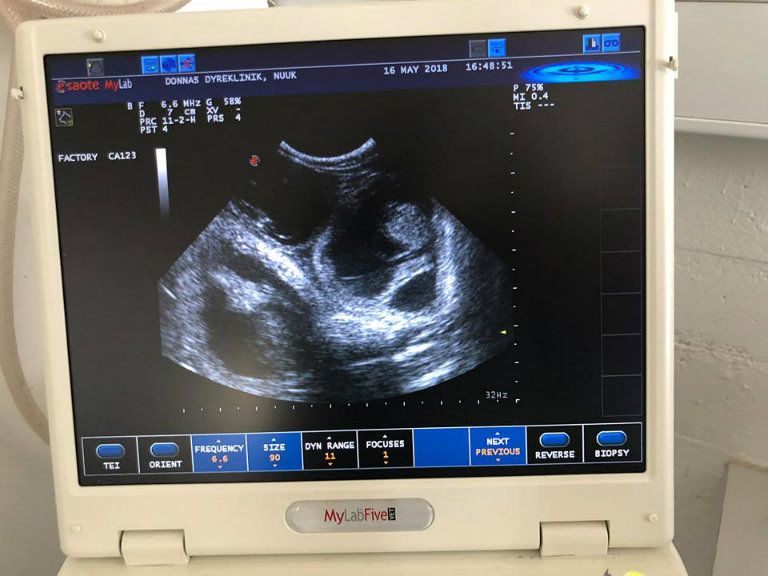

Amikor orvoshoz vitték, az ultrahang megmutatta, hogy négy-öt kismacska növekszik az állat pocakjában.

Fotó: Dyrenes Venner/Facebook